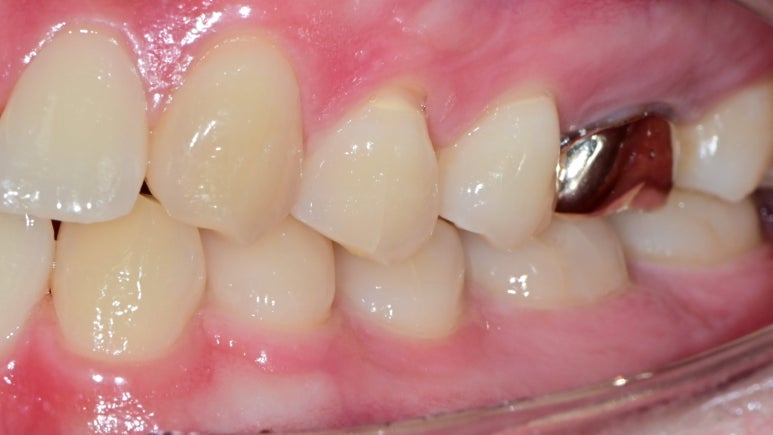

☑️ 증상 관찰: 치아 마모 + 실금 + 교합 문제

환자분의 상악 제1, 2소구치 / 하악 제1소구치

모두에서 치경부 마모가 관찰되었고,

**견치(송곳니)**의 끝부분도 마모된 상태였습니다.

또한 치아 표면에는

- 마모(Attrition)

- 작은 실금(Craze line)

- 쐐기 모양 치경부 마모(Abfraction)

등이 함께 확인되었습니다.

☑️치료 전후 비교

- 치료 전: 치경부 패임, 마모, 교합 불균형

- 치료 후: 레진 수복 + 교합 안정화로 기능 및 심미성 개선

한눈에 보기에도

치아 형태와 기능이 자연스럽게 회복된 모습을

확인하실 수 있습니다.